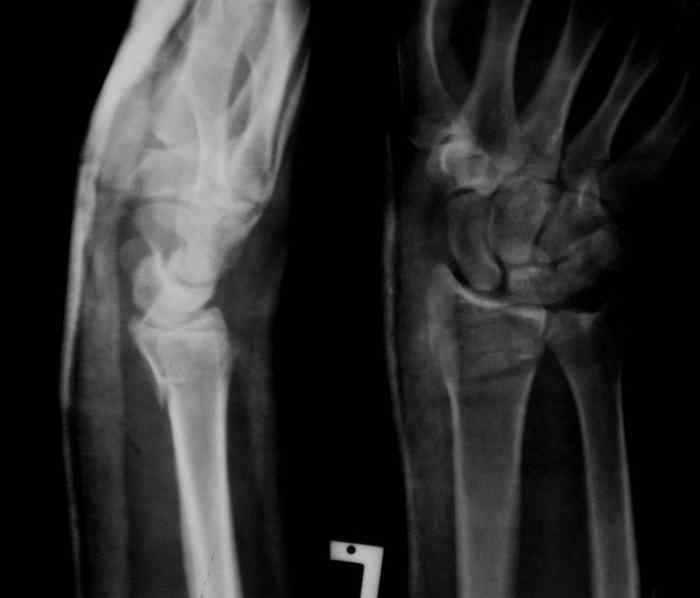

Под проводниковой анестезией произвел аккуратную одномоментную репозицию, фиксацию гипсовой повязкой в положении умеренной экстензии. Думаю неплохо получилось. Мягкие ткани не вызывали опасений в плане Зудека.